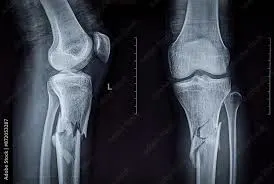

Long bone structure parts

diaphysis, epiphyses, compact bone, spongy bone, medullary cavity

Epiphysis definition

ends of long bone

Compact bone function

strength and protection S

Spongy bone structure and function

•provide structural support

•house red bone marrow for blood cell production